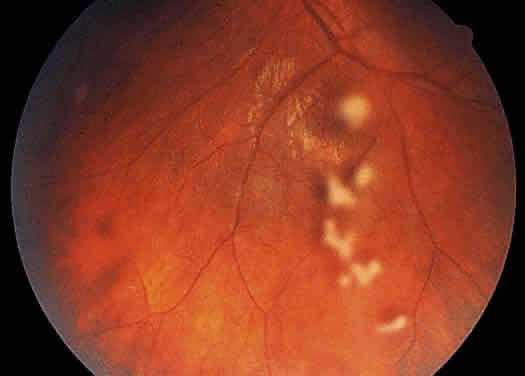

The retinal vessels should be examined for evidence of vasculitis, noting whether the vasculitis affects primarily the veins (phlebitis) or the arteries (arteritis). Patients with sarcoid uveitis commonly have extensive periphlebitis, whereas patients with Behçet's disease may have more of an arteritic picture. Patients with herpetic retinitis may have extensive arteritis and phlebitis, which produce the appearance of “frosted branch angiitis”37 (Fig. 13).

Fig. 13. Fundus photograph of the right eye of a patient with cytomegalovirus retinitis and extensive “frosted branch angiitis.” The active cytomegalovirus retinitis is temporal to the fovea and along the superotemporal arcade.